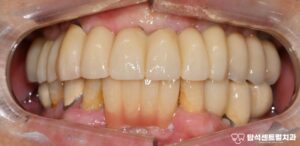

용현동 치과 외상으로 앞니 흔들림 있을 때, 치아를 보존하는 마지막 방법 : 잠간 고정술 설명 (+입술 봉합)

안녕하세요 용현동 치과 입니다. 빙판길 낙상, 구강 부상의 원인이 될 수 있습니다 겨울철에는 도로와 인도가단단하게 얼어붙는 경우가 많습니다.이런 빙판길에서 미끄러지면손을 짚기도 전에 얼굴부터바닥에 부딪히는 사고가 발생합니다. 특히 전치부는 충격에 취약한위치에…